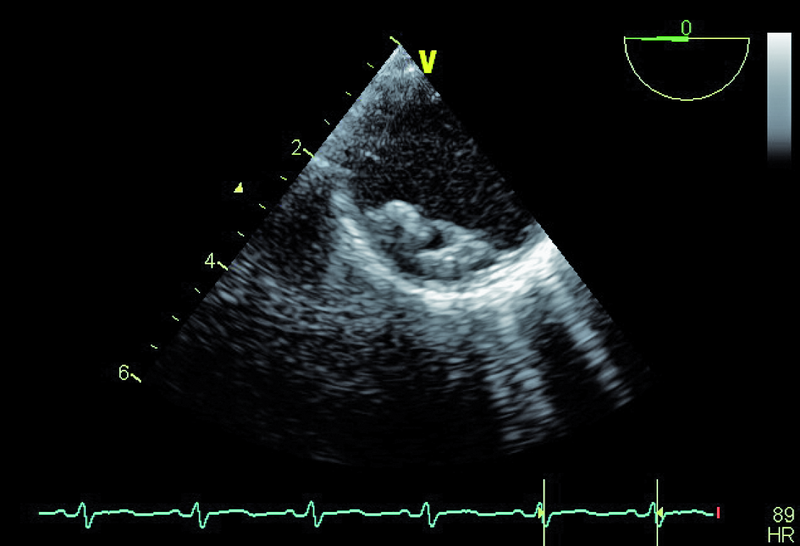

Pacjent, lat 60, z wywiadem nadciśnienia tętniczego, wieloletni palacz, został przyjęty do kliniki w celu oceny układu krążenia po przebytym rok wcześniej udarze mózgu. W przebiegu udaru obserwowano afazję ruchową, niedowład centralny nerwu VII, niedowład prawej kończyny górnej. Chory był intensywnie rehabilitowany, co przyczyniło się do stopniowego ustąpienia zaburzeń mowy oraz istotnej poprawy ruchomości prawej kończyny górnej. W tomografii komputerowej stwierdzono obszar hipodensyjny na pograniczu płata ciemieniowego i potylicznego lewej półkuli mózgu. Spektralne badanie doplerowskie tętnic szyjnych i kręgowych nie wykazało istotnych hemodynamicznie zaburzeń przepływu. Opiekujący się pacjentem neurolodzy podejrzewali, że przyczyną udaru mógł być przetrwały otwór owalny (patent foramen ovale, PFO). W wykonanych w klinice badaniach echokardiograficznych – przezklatkowym i przezprzełykowym – przegroda międzyprzedsionkowa była szczelna. Jama lewej komory była niepowiększona, a grubość mięśnia graniczna. Zwracało uwagę nieznaczne upośledzenie kurczliwości mięśnia komory (EF=50%) oraz poszerzenie aorty do 42 mm.

Wiek pacjenta, palenie tytoniu oraz chwiejne nadciśnienie tętnicze nakazują wykluczyć a priori tzw. kryptogenny udar mózgu. Przegroda międzyprzedsionkowa u chorego była szczelna, choć w badaniu przezprzełykowym (TOE) opisano śladowy kanał przetrwałego otworu owalnego (PFO), bez przechodzenia kontrastu ze strony prawej na lewą. Badanie przezprzełykowe pozwoliło także wykluczyć skrzeplinę w jamach serca (ryc. 1 – uszko lewego przedsionka) oraz istotne zmiany organiczne zastawki aortalnej (ryc. 2, 3). Prawdopodobną przyczyną udaru były nasilone zmiany miażdżycowe w łuku aorty z towarzyszącymi owrzodzeniami ściany naczynia (ryc. 4, 5). Warto zaznaczyć, że zmiany będące zgrubieniem błony wewnętrznej bywają dynamiczne i nie można wykluczyć powstawania ruchomych składowych (skrzeplin) na dużych elementach owrzodzenia. W diagnostyce miażdżycowego uszkodzenia aorty metodą z wyboru jest badanie przezprzełykowe, pozwalające zidentyfikować dzięki wysokiej rozdzielczości obrazu drobne, nawet kilkumilimetrowe owrzodzenia. Warto zaznaczyć, że badanie przezklatkowe nie dostarcza tak wyraźnego i jednoznacznego obrazu (ryc. 6). Korzyść z badania echokardiograficznego jest bez wątpienia większa niż z badania TK czy MR, ze względu na możliwość oceny ruchomości blaszek w czasie rzeczywistym. W rutynowej ocenie zwraca się uwagę na grubość blaszki miażdżycowej, obecność owrzodzeń, zwapnień oraz nałożonych ruchomych ech odpowiadających skrzeplinom – stanowiących tzw. potencjał zatorowy blaszki. Uważa się, że średnica blaszki przekraczająca 4 mm ma większy potencjał zatorowy niż owrzodzenie płytkie (w przedstawionym przypadku średnica blaszki wynosiła 7 mm). Dowiedziono ponadto, że w przypadku blaszek nieuwapnionych – jak w opisanej sytuacji – ryzyko zatoru jest większe niż w przypadku blaszek uwapnionych. Leczenie antykoagulacyjne w takim wypadku jest uzasadnione. Konieczne jest także włączenie dużej dawki statyn mimo braku zmian miażdżycowych w tętnicach wieńcowych (wykonano koronarografię). Ocena układu krążenia u pacjenta po przebytym incydencie zatorowym do OUN powinna być kompleksowa i powinna uwzględniać wszystkie możliwe nieprawidłowości.